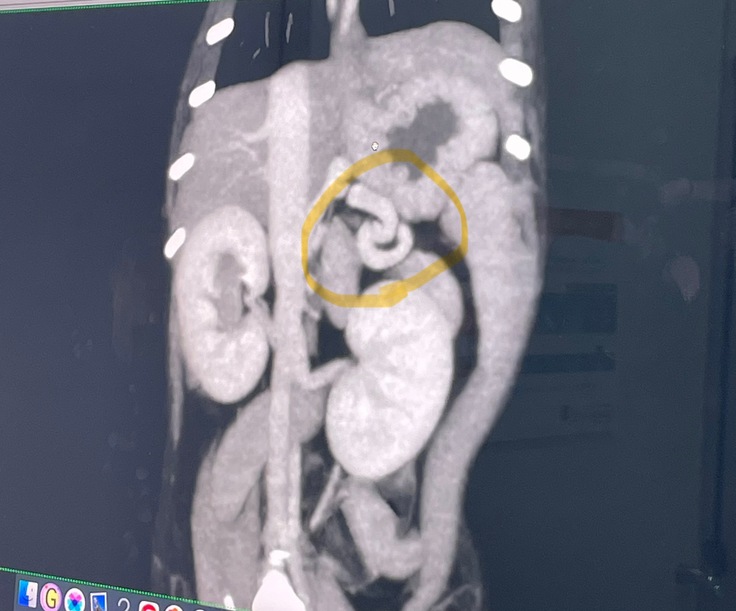

想像を超える大手術

1回目の手術の写真です。

※2枚目に【手術中の写真】があります。

苦手な方はご注意ください

想像を超える大手術。生後6ヶ月の小さな体でこの手術を2回も行わなければ、ぱんちゃんは助かりません涙